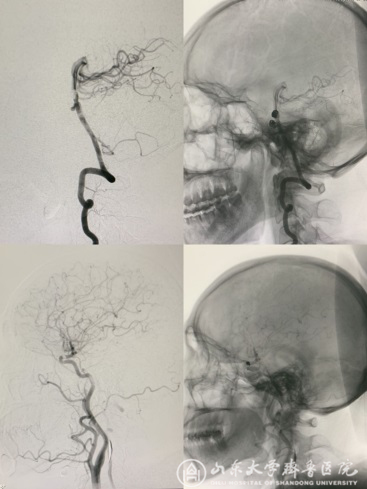

【本站讯】为响应国家卫健委关于“深化医保支付方式改革,开展日间手术”的号召,在住院处、手术室等科室大力支持下,神经外科脑血管病区在国庆期间开展了5例“经桡动脉全脑血管造影日间手术”,目前所有病人已完成院外随访,恢复良好。 近日,王东海教授手术团队为多名颅内动脉瘤栓塞术后的患者进行了经桡动脉入路脑血管造影复查。为推动该项日间手术的尽快开展,王东海教授提前与相关科室和职能部门沟通完善患者住院时间和检查流程;在门诊对患者进行综合评估,与患者及家属精心沟通;假期期间由主治医师邓林、张平实施“经桡动脉全脑血管造影日间手术”,过程顺利,达到了预期检查效果(图-1)。为患者进行了日间经桡动脉脑血管造影术。

图-1两例脑动脉瘤栓塞术后日间手术复查造影,图像清晰,完全满足诊断需要。